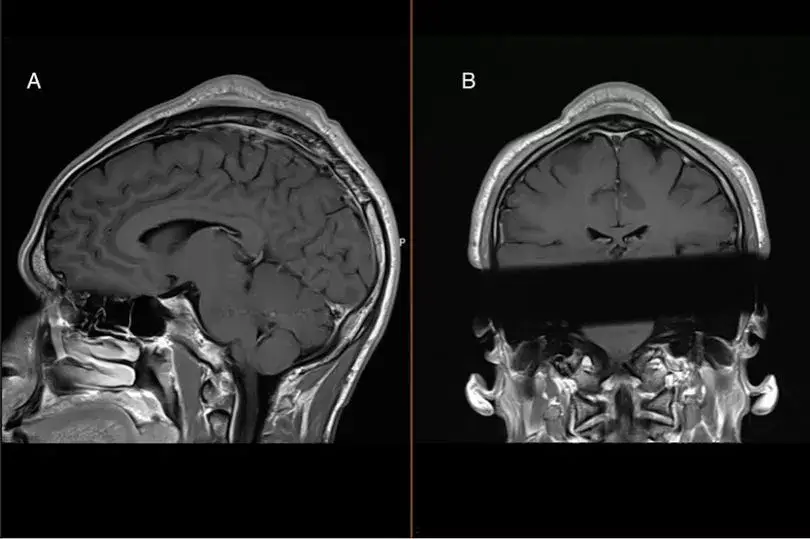

As it turned out, it was his dance moves that caused the lump of tissue to form, and when his brain was scanned, they noted an even more surprising thing: a mass.

Instead of finding a cancerous tumor, they believed what they were seeing was a rare case of ‘headspin hole’, which is a benign tumor made up of tissue.

The doctors also noticed that the skin above the bump moved easily, which suggested that this mass was formed in between the skin and the skull - which the scan confirmed to be true.